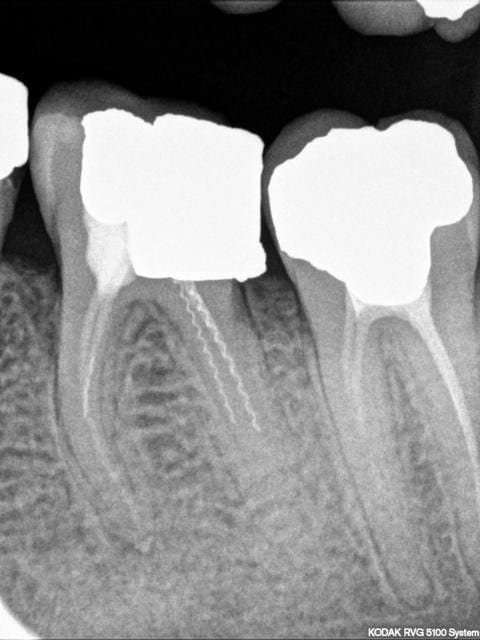

est ce le meme lentulo?

ils ne devraient pas être trop dur à enlever

ds l'autre canal,une broche?

et l'apex intègre!!:)

non y'a une lesion en mesial...

Mieux vaut 2 lentulos cassés sans pâte qu'une mauvaise obturation!